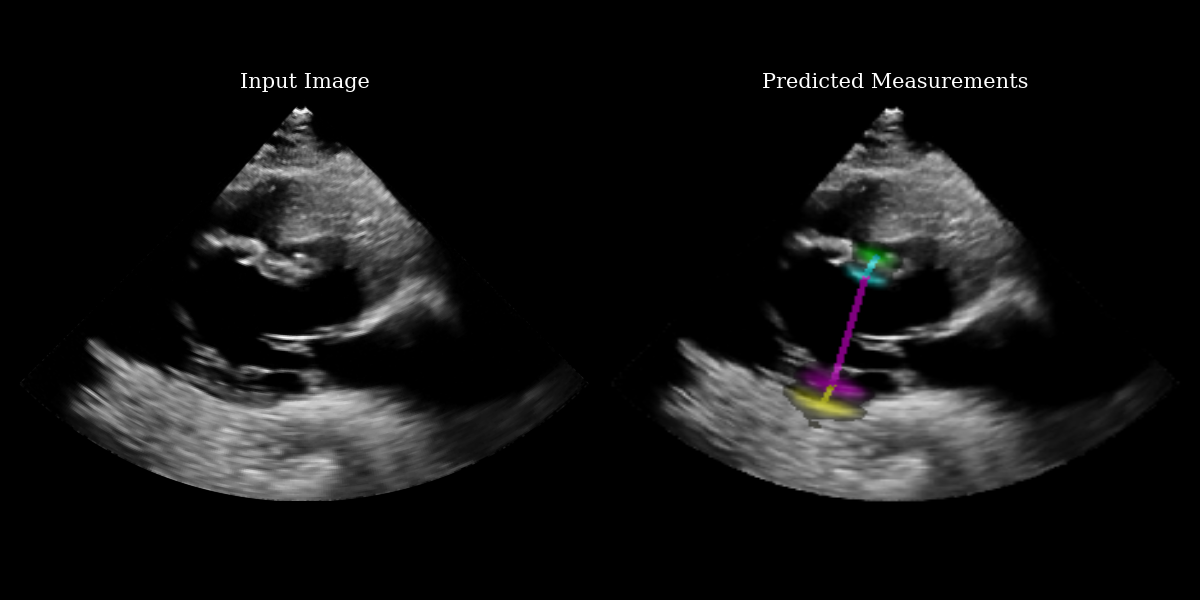

# use visualization function to visualize heatmaps and measurement lines on the input image

images_with_measurements = model.visualize_logits(batch, logits)

# Plotting

fig, (ax1, ax2) = plt.subplots(1, 2, figsize=(12, 6))

# Plot input image

ax1.imshow(img_np, cmap="gray")

ax1.set_title("Input Image", fontsize=15)

ax1.axis("off")

# Plot output with measurements

ax2.imshow(images_with_measurements[0])

ax2.set_title("Predicted Measurements", fontsize=15)

ax2.axis("off")

EchoNetLVH Example Output